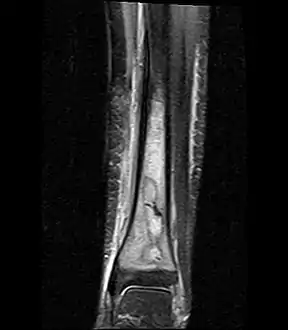

Fat saturated STIR (short tau inversion recovery) image showing hyperintense edema in the calf musculature, marrow edema, and subperiosteal pus. The intramedullary abscess cavity is hyperintense as well.